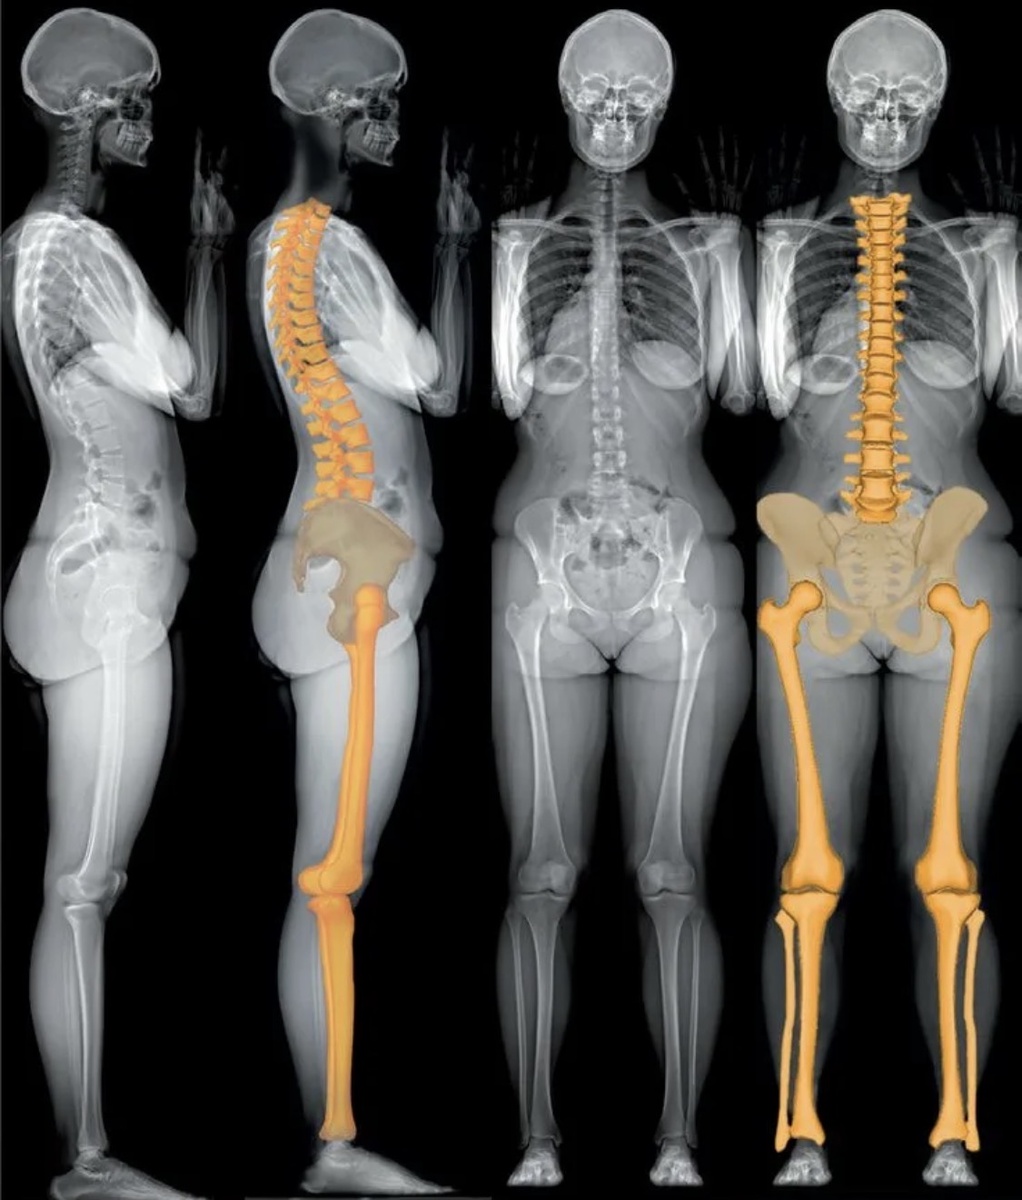

Выяснить разницу на глаз или с помощью рулетки не получится. Примерно - да. Истинный дефицит можно посчитать только по телерентгенограмме, или рентгеновской сшивке. Это когда рентгенолог на цифровом оборудовании делает подряд рентгенограммы скелета стоящего человека, затем компьютер «сшивает» все изображения в одну картинку, и мы на компьютере же в специальной программе вычисляем длину каждой кости, видим её форму, оцениваем ситуацию в целом.

Примерно так

Или так